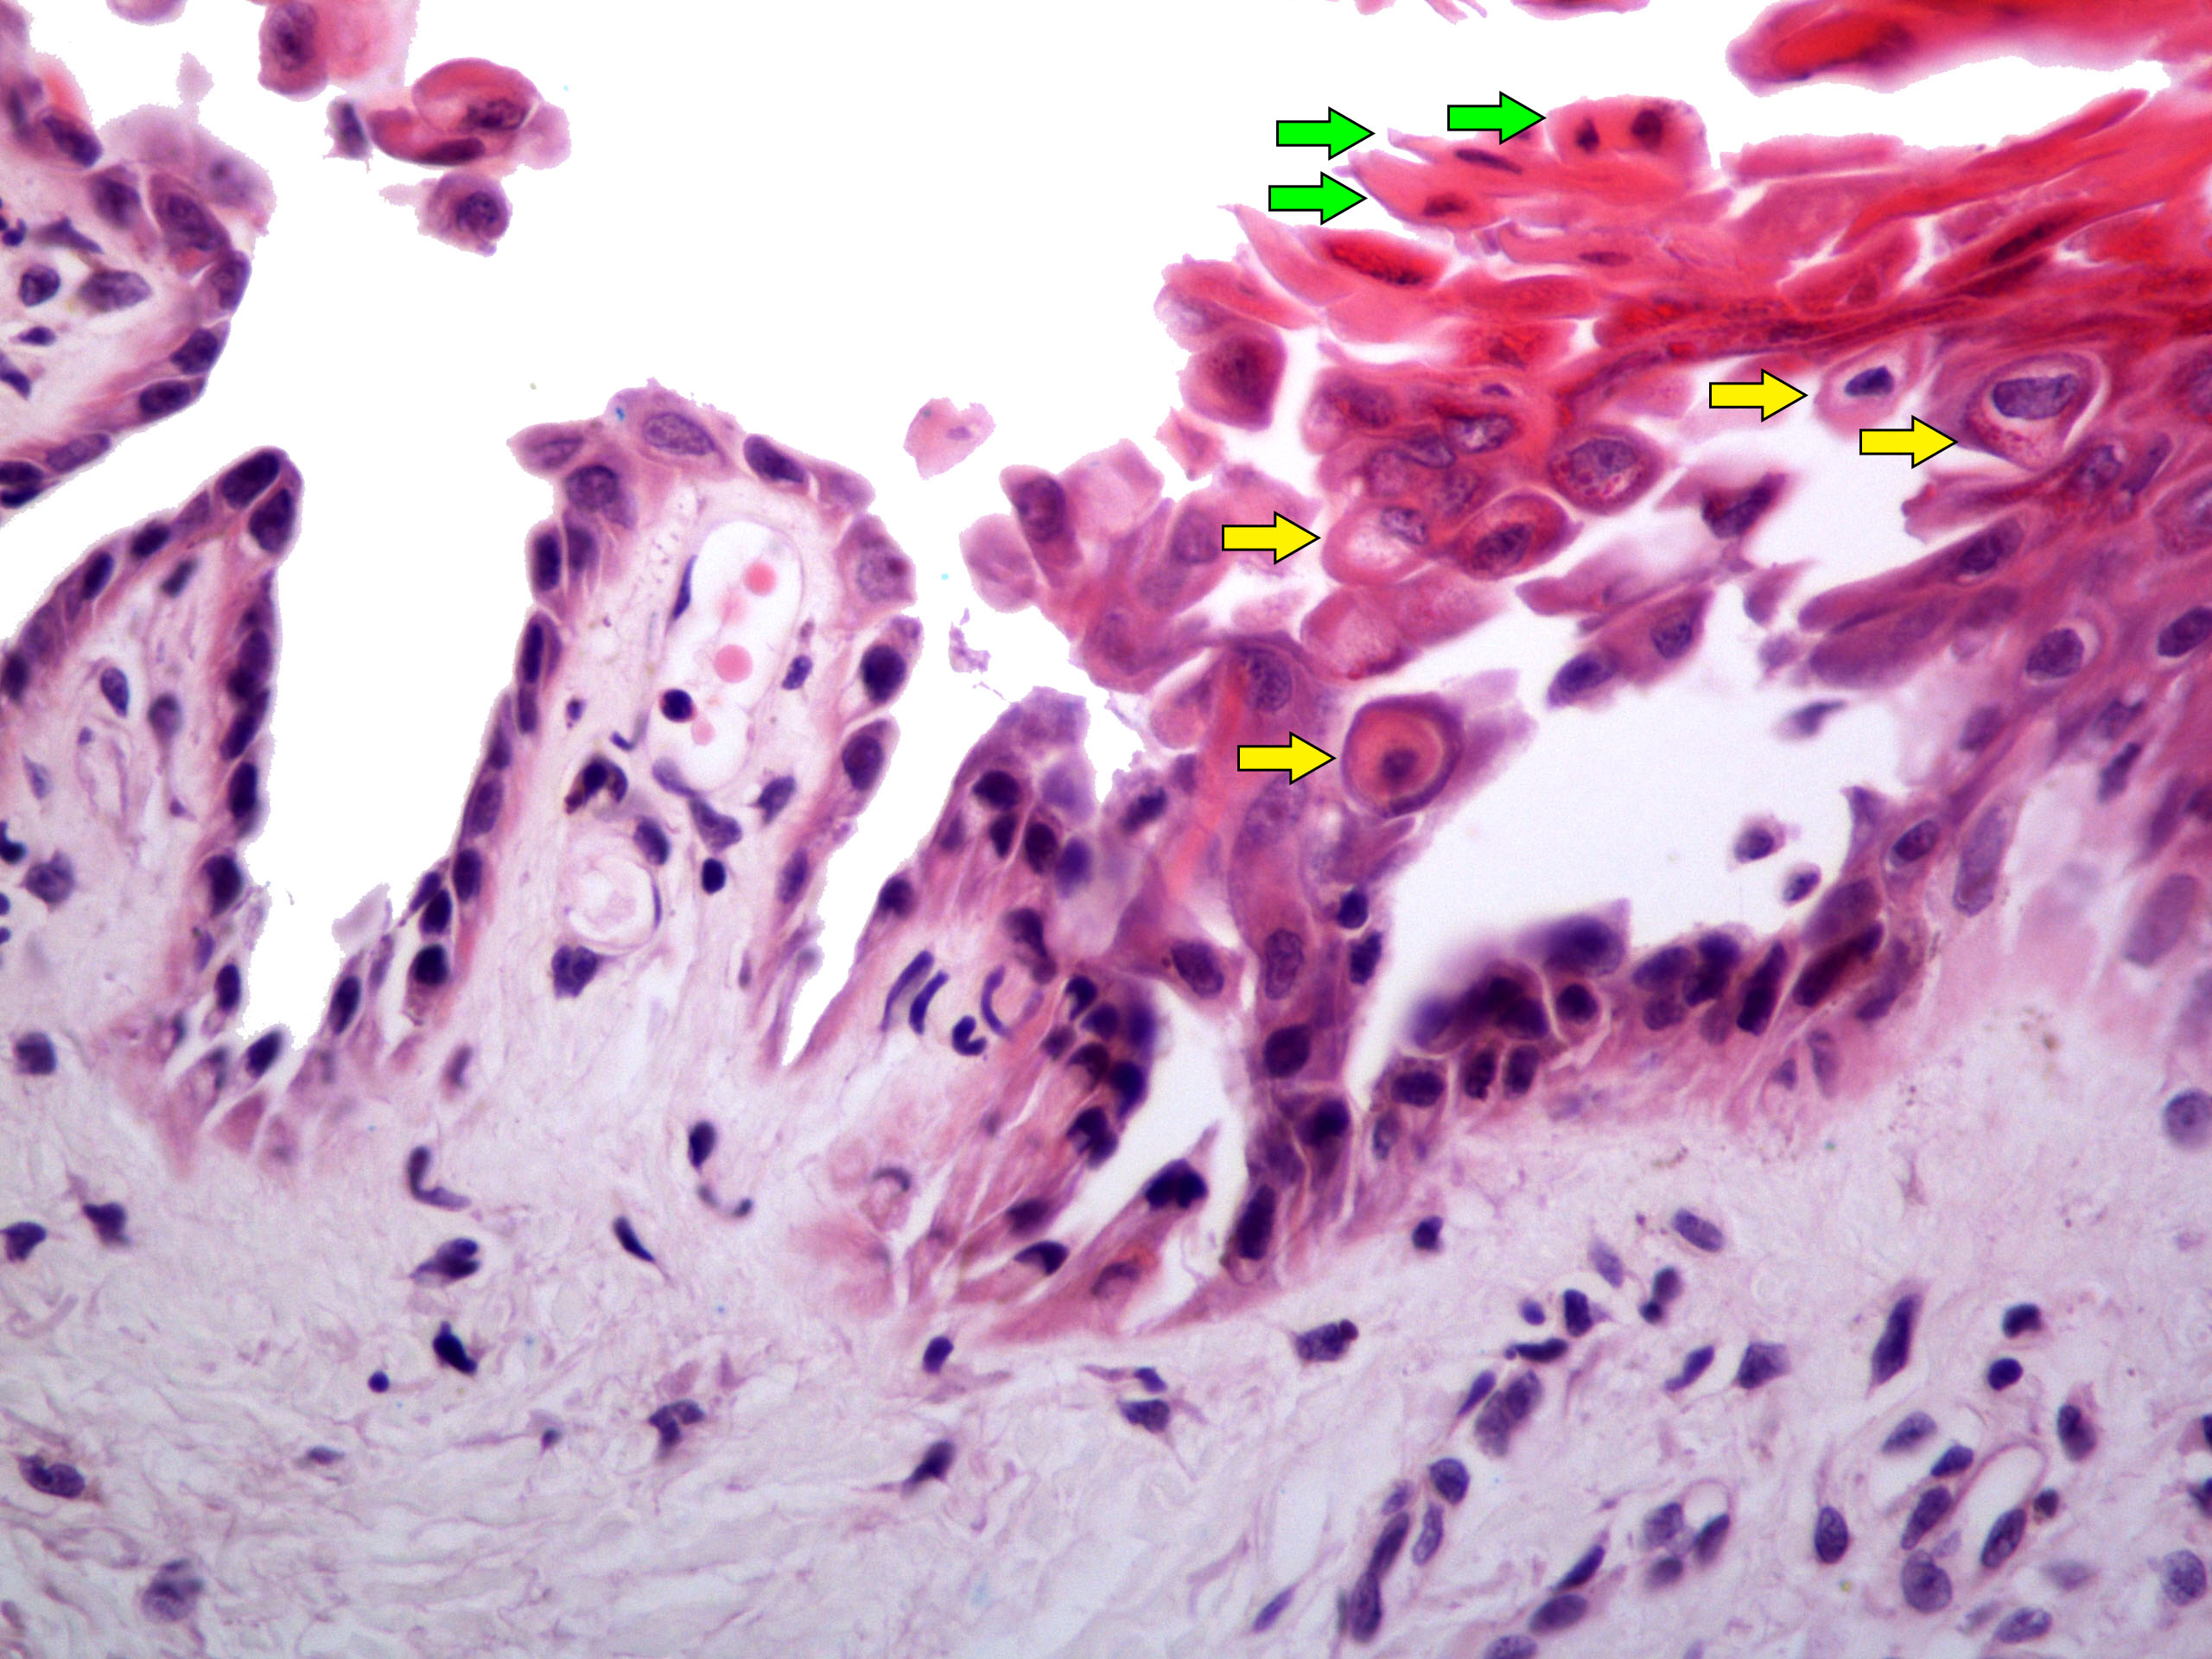

Microscopic (histologic) description

- Acantholysis with characteristic dyskeratosis forming corp ronds and grains

- Corp rond: rounded keratinocyte in superficial spiny and granular layer with basophilic / pyknotic nucleus, perinuclear halo and often a rim of eosinophilic cytoplasm (J Dermatol 2017;44:232)

- Grain: elongated keratinocyte in the stratum corneum with small basophilic nuclei and intensely pink cytoplasm; appears as plump parakeratosis; may form tiers (J Dermatol 2017;44:232)

- Corp rond and grain type dyskeratosis is classical but not specific for Darier disease (see Differential diagnosis)

- Suprabasal acantholysis and clefting with retained single layer of basal keratinocytes overlying dermal papillae which appear to project into the acantholytic cavity (villi) (J Dermatol 2016;43:275)

Microscopic (histologic) images